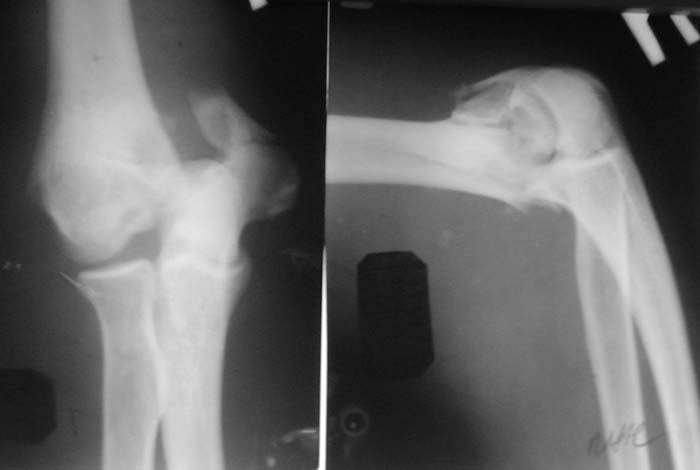

Солидарен с мнением обоих Александров (Челнокова и Рыкова): точную репозицию такого перелома вряд ли удастся выполнить закрыто. Даже во время открытого вмешательства это сделать непросто. Неслучайно предложен костно-пластический доступ с временным отсечением локтевого отростка. И по методу фиксации согласен с Александром Челноковым: 2 пластины. В качестве примера привожу рентгенограммы одного из наших пациентов с аналогичным повреждением.

С уважением, А. Золотов, Приморский край.

Alexander Artemiev 14 Сентябрь 2005, 16:19

Снимки - во вложении.

Женщина 42 лет, операция через неделю после перелома.

Д-з - открытый перелом мыщелков со смещзением и локтевой кости

без смещения - падение с лошади.

До операции снимки не очень, тем более в гипсе.

Остеосинтез закрытый (если так можно выразиться), т.е. без

разрезов. Длительность операции - около 1,5 часа со студентом.

6 щелчков ЭОПом.